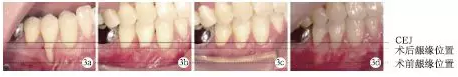

術前#44頰側牙齦退縮達9mm;術后兩周、術后兩個月及術后1年,頰側齦退縮減少為2mm,根面覆蓋率為:77.8%,未見進行性牙齦退縮(圖3)。

圖3 術前及術后根面牙齦覆蓋情況對比

術前#44頰側角化齦寬度極少,小于1mm;術后2個月及術后1年,可見角化齦寬度增加為2mm,且角化齦厚度也明顯增加,見圖4。

圖4 術前及術后頰側角化齦寬度對比